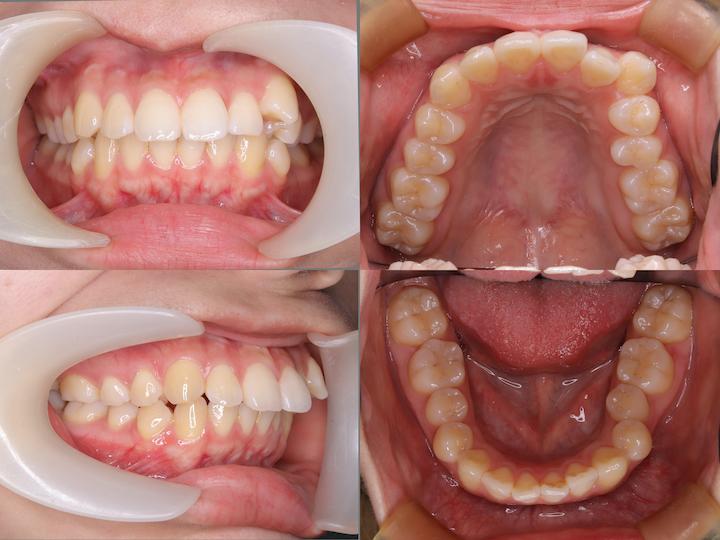

本症例は、上下顎前歯部の著しい叢生および犬歯の低位唇側転位(八重歯)を主訴とする患者様に対し、上下顎ともに舌側矯正装置を使用して治療を行いました。

高度なアーチレングスディスクレパンシーを改善するため、上下小臼歯の計4本を抜歯し、適切な咬合関係の確立を図りました。

主訴:上下前歯部の叢生および犬歯の低位唇側転位(八重歯)

初診時の口腔内所見として、以下の不正咬合が認められました。・上下顎前歯部の重度叢生

・犬歯の低位唇側転位(八重歯)

・著しいアーチレングスディスクレパンシー

・AngleⅡ級臼歯関係(下顎大臼歯の後方位)

・口唇部の突出感は認められない